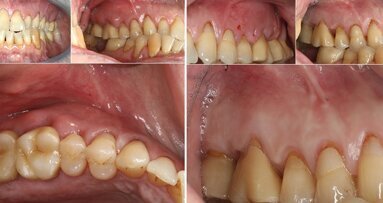

El autor describe las ventajas de la cirugía piezoeléctrica para la extracción atraumática de dientes. Esta tecnología ultrasónica permite realizar también cirugía pre-implantaria de forma segura y precisa, dando como resultado un mejor post-operatorio y una significativa reducción del dolor para el paciente.

La cirugía piezoeléctrica es una técnica desarrollada para el corte de hueso de manera precisa y atraumática basada en microvibraciones ultrasónicas a través del uso de cristales de cuarzo, los cuales vibran al ser estimulados por una corriente eléctrica, generando movimientos oscilantes que son transmitidos al inserto. El inserto tiene una actividad selectiva sobre los tejidos duros calcificados como pueden ser el hueso y el diente, mientras que el tejido blando absorbe la vibración y no produce ningún tipo de daño sobre los tejidos, ventaja importante cuando realizamos osteotomías en áreas afectadas por vasos o nervios o en técnicas de mejora de seno maxilar, donde se respeta la membrana de Schneider, del mismo modo cuando estamos trabajando cerca de la encía o mucosa alveolar.